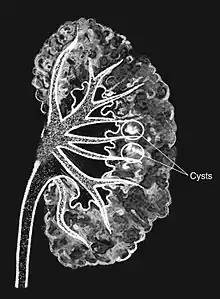

Medullary sponge as seen on an intravenous pyelogram | |

Medullary sponge kidney is a congenital disorder of the kidneys characterized by cystic dilatation of the collecting tubules in one or both kidneys. Individuals with medullary sponge kidney are at increased risk for kidney stones and urinary tract infection (UTI). Patients with MSK typically pass twice as many stones per year as do other stone formers without MSK. While having a low morbidity rate, as many as 10% of patients with MSK have an increased risk of morbidity associated with frequent stones and UTIs. While many patients report increased chronic kidney pain, the source of the pain, when a UTI or blockage is not present, is unclear at this time. Renal colic (flank and back pain) is present in 55% of patients. Women with MSK experience more stones, UTIs, and complications than men. MSK was previously believed not to be hereditary but there is more evidence coming forth that may indicate otherwise.[1][2]

Classically, MSK is seen as hyperechoic papillae with clusters of small stones on ultrasound examination of the kidney or with an abdominal x-ray. The irregular (ectatic) collecting ducts are often seen in MSK, which are sometimes described as having a "paintbrush-like" appearance, are best seen on intravenous urography. However, IV urography has been largely replaced by contrast-enhanced, high-resolution helical CT with digital reconstruction.[8]